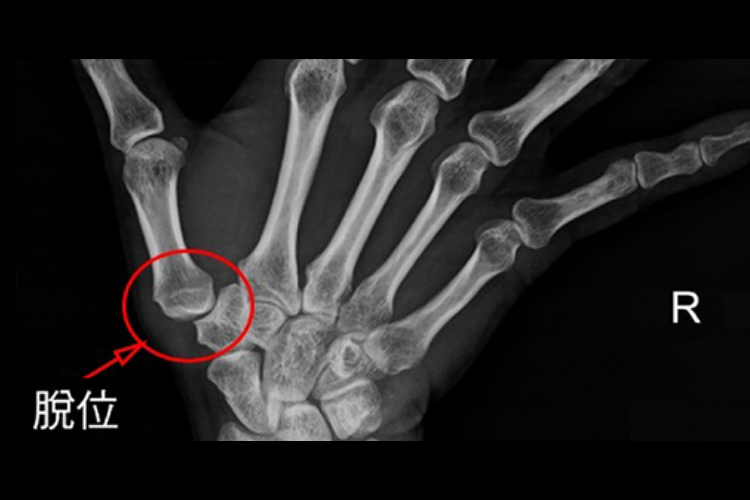

5、创伤性关节炎:

- 拇指关节曾受过外伤,如扭伤、撞伤等,即使伤口愈合,也可能遗留创伤性关节炎。

- 关节疼痛在活动或受力时加重。治疗包括休息、理疗、口服止痛药物等。若症状严重,可能需要进行关节融合或置换手术。